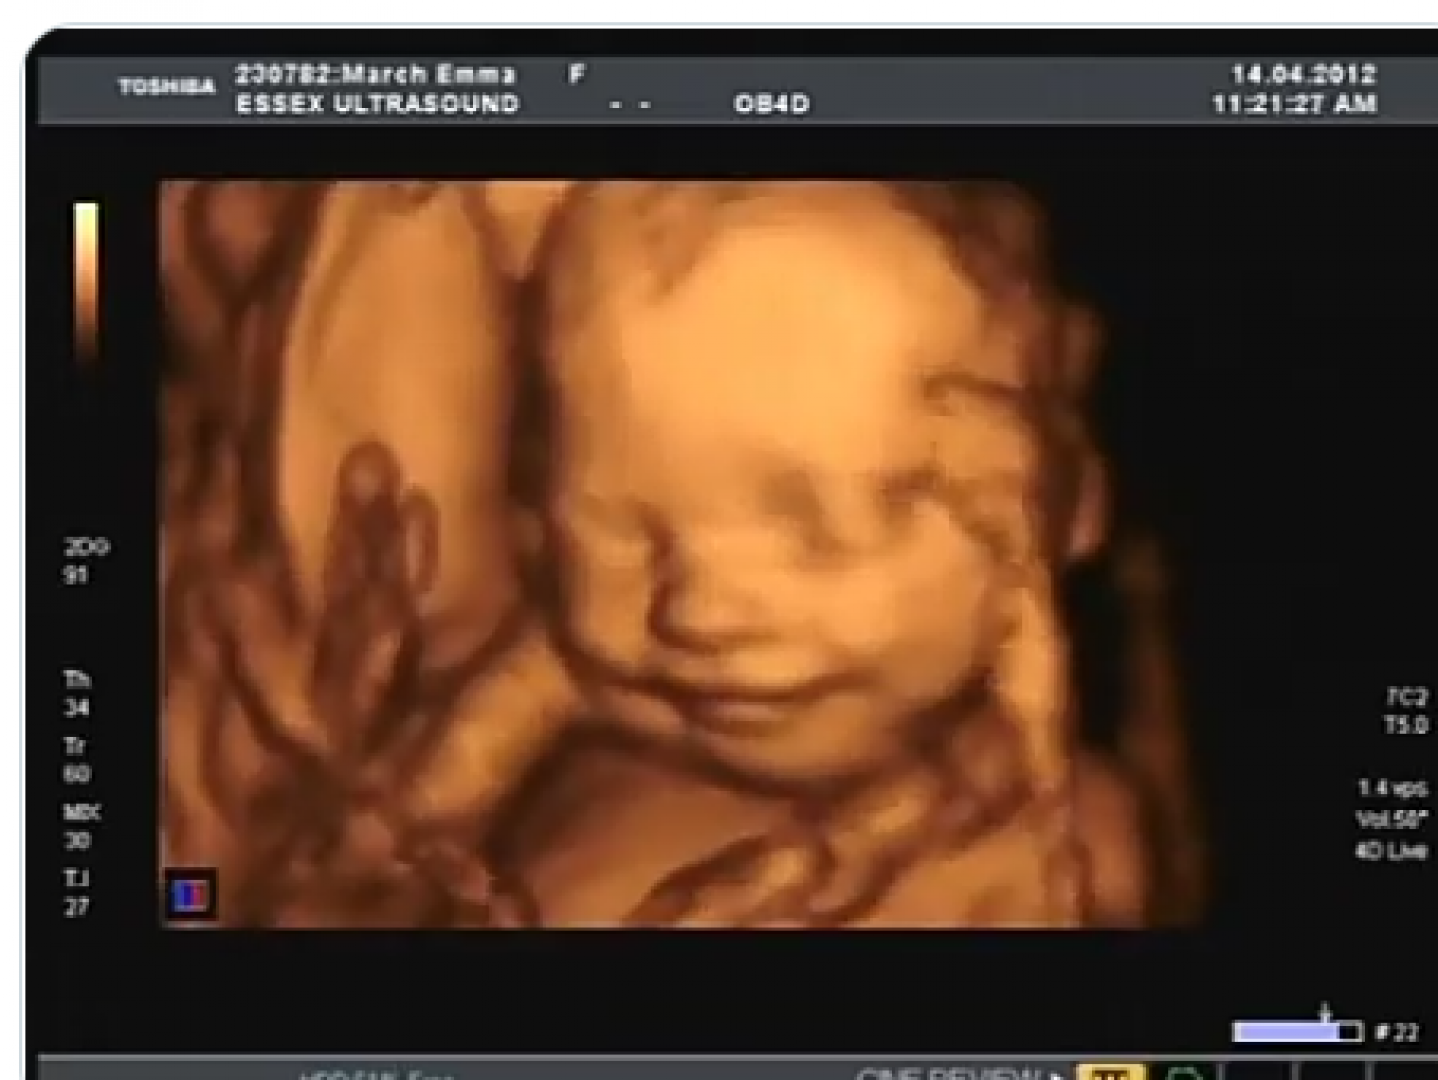

عقب الفحوصات علم الطبيب أنها مازالت حامل في الأشهر الأولى، أخبرها أن تحديد نوع الجنين يكون في بدايةً من الشهر الرابع، وبالفعل انتظرت عدة أهش لتحديد نوع الجنين من خلال فحص الموجات الفوق صوتية.

يكون جهاز الموجات هو من الأجهزة الأكثر شيوعًا واستخدمًا بين الأطباء في تحديد نوع الجنين، حيث يفضل إجراؤه في منتصف أشهر الحمل؛ لتكون النتائج أكثر دقة، ولكنه ليس دقيقًا كثيرًا؛ نظرًا لكونه يعتمد على عدة عوامل منها

- مهارة الطبيب، وقدرته على قراءة الأمور الظاهرة على الشاشة.

- إذا كانت الأعضاء التناسلية صغيرة للجنين، تكون سببًا في إعاقة تحديد الجنس.

- يمكن الخلط بين الحبل السري، والأعضاء التناسلية في بعض الأحيان.